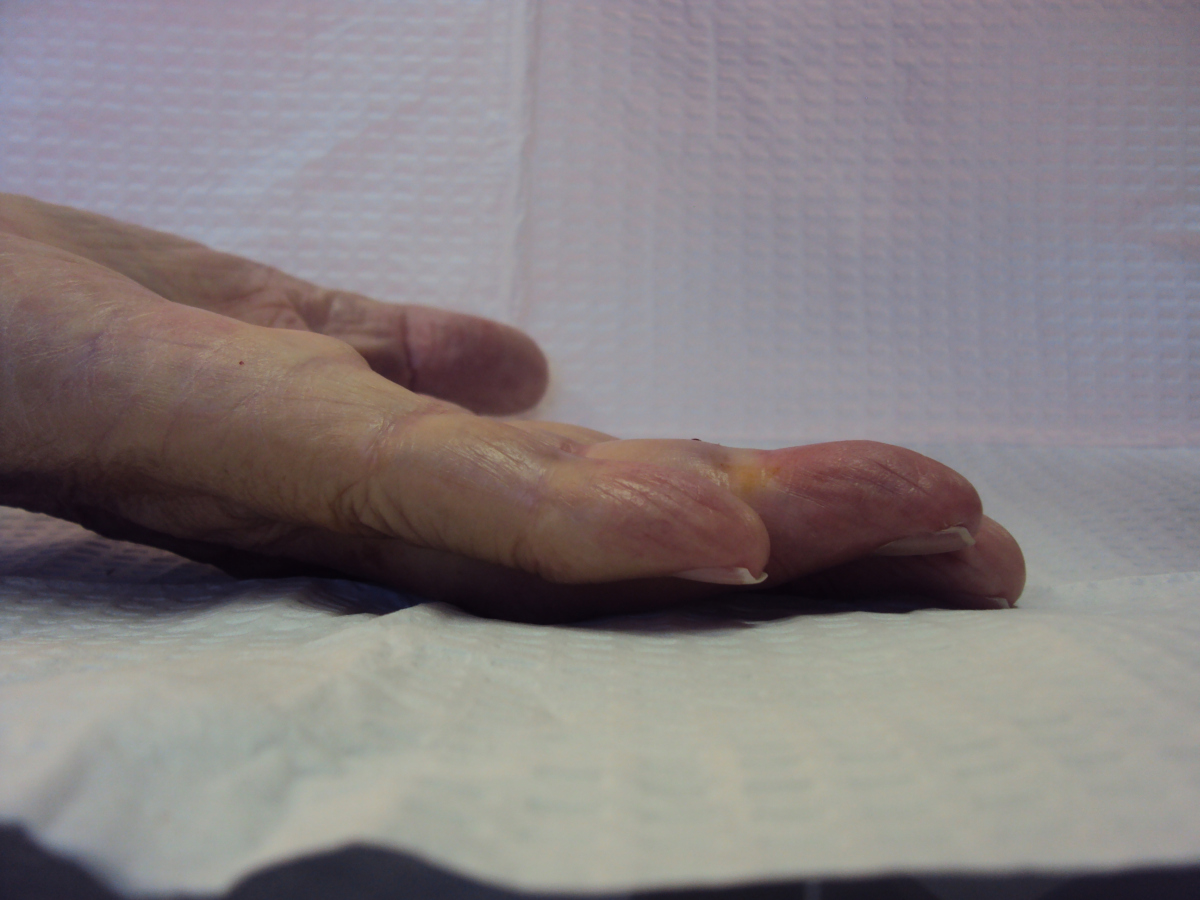

Case 4.

57 year old right handed man with a 22 year

history of Dupuytren disease affecting his

left small finger.

Planning of portals (dots) and nodule steroid

injection sites (circles).